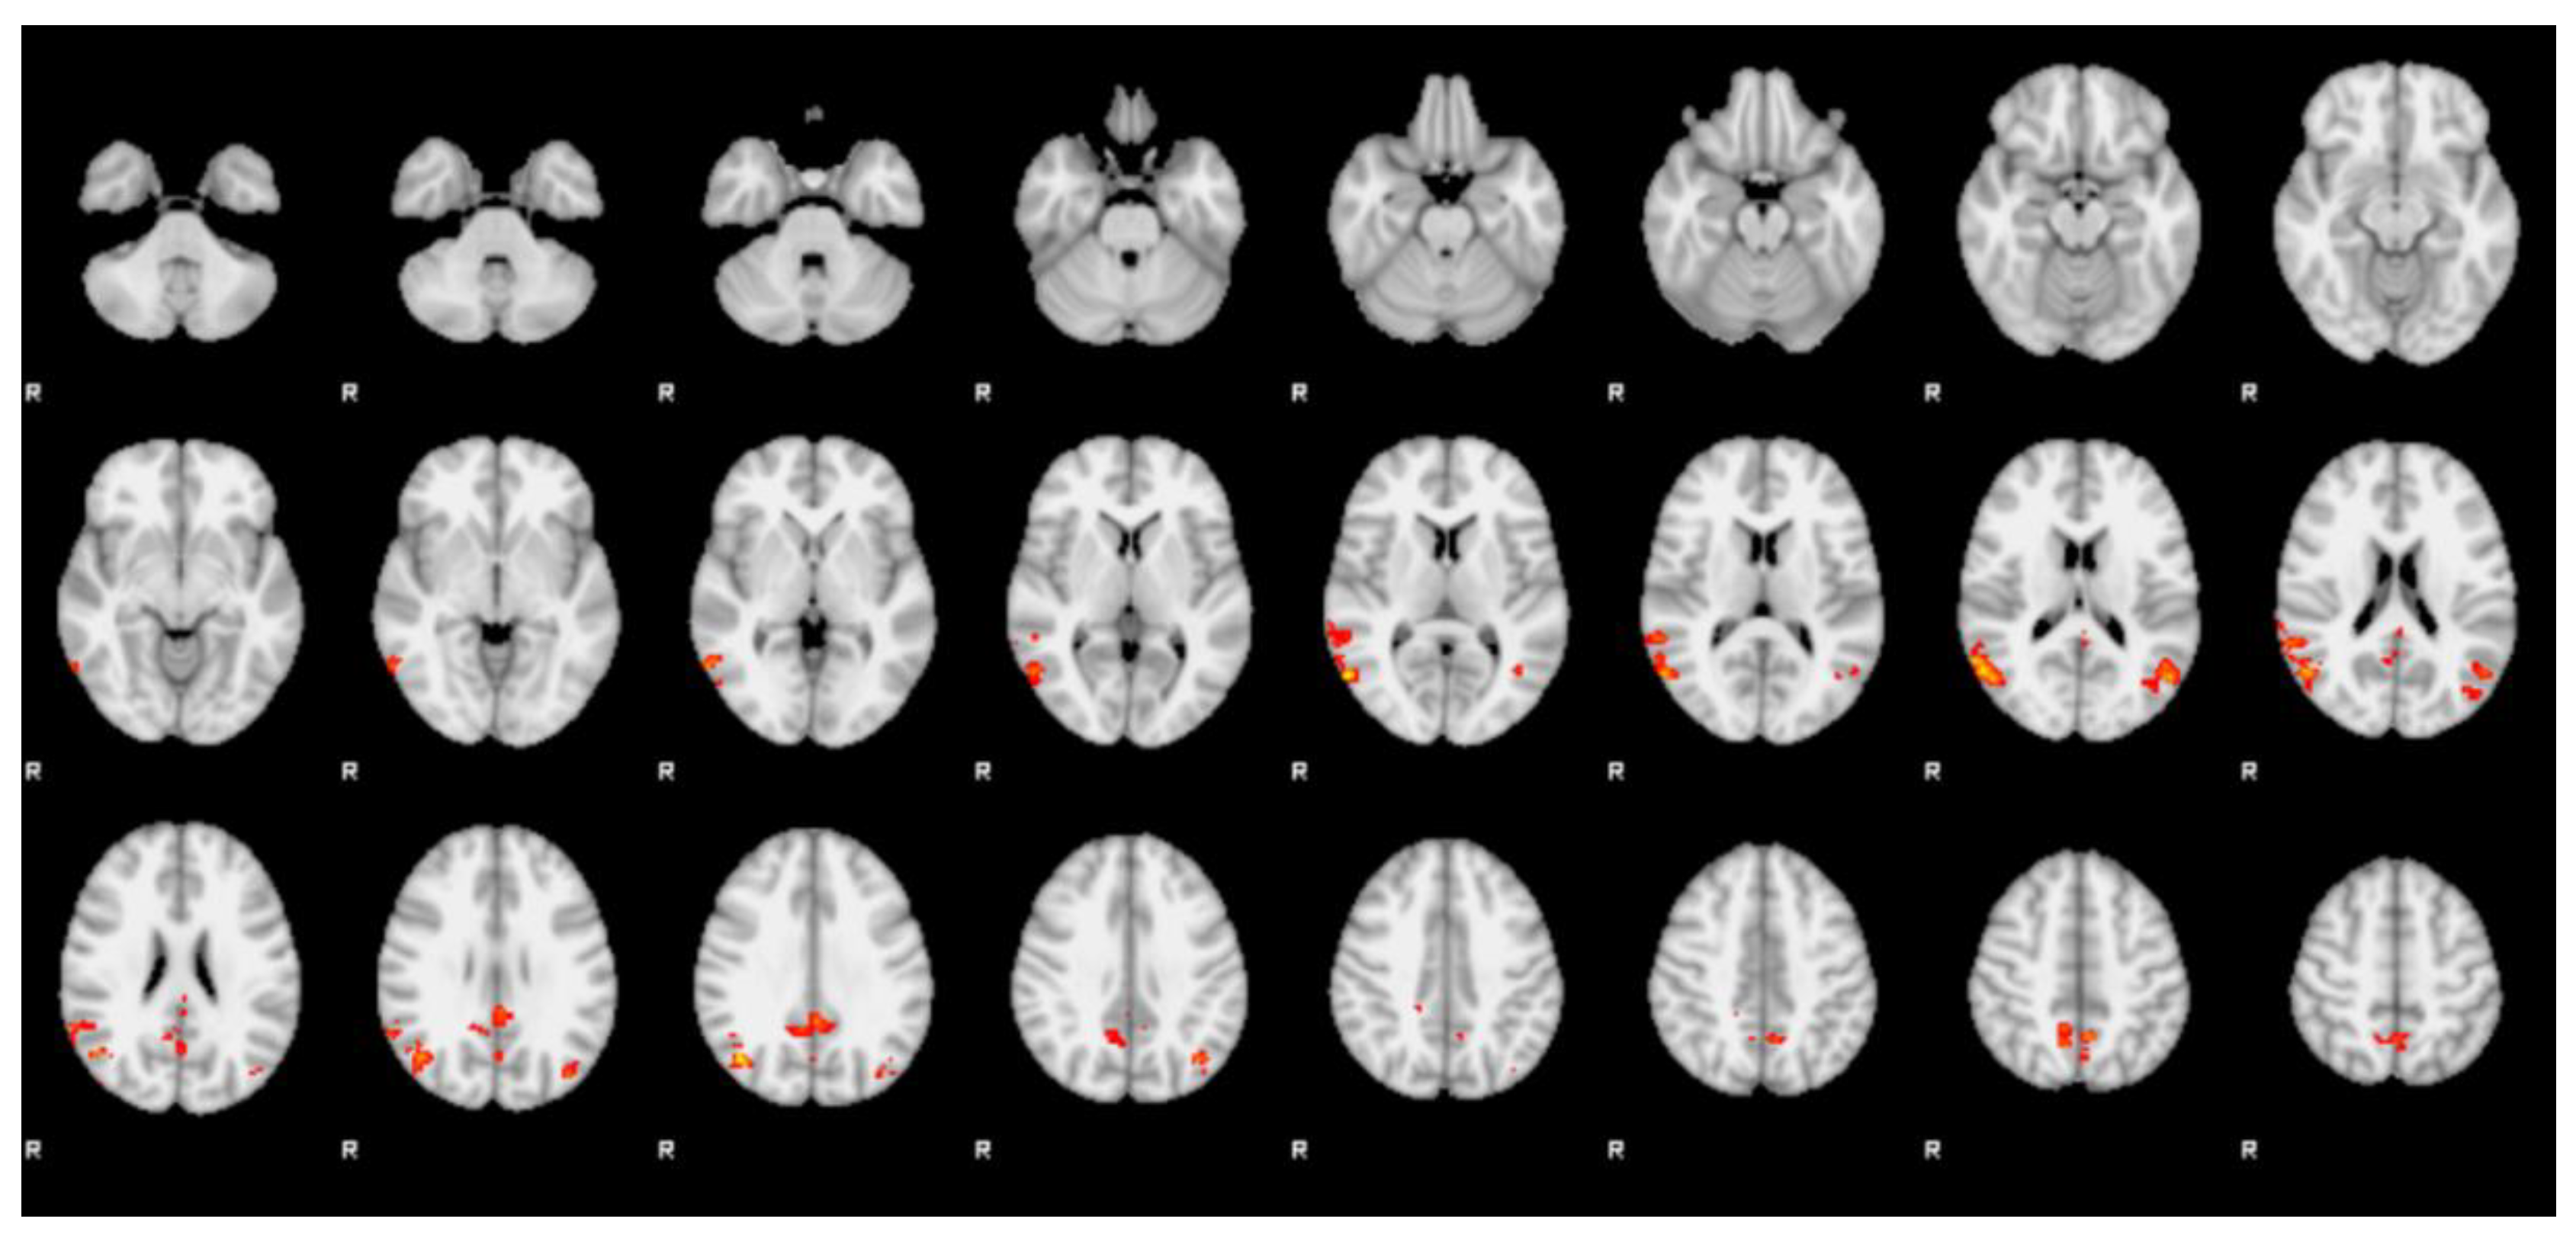

3.2. fMRI

| Cluster | Z-stat | x (mm) | y (mm) | z (mm) | Region (Harvard) |

|---|---|---|---|---|---|

| 1 | 3.01 | −14 | −54 | 26 | left precuneus cortex |

| 3.01 | 0 | −56 | 14 | left precuneus cortex | |

| 3 | −6 | −56 | 16 | left precuneus cortex | |

| 2.89 | −2 | −60 | 16 | left precuneus cortex | |

| 2.82 | −2 | −62 | 8 | left precuneus cortex | |

| 2.74 | 4 | −56 | 22 | right precuneus cortex |

| 1 | 3.99 | 58 | −66 | 8 | right lateral occipital cortex |

| 3.9 | 44 | −68 | 30 | right lateral occipital cortex | |

| 3.71 | 56 | −62 | 16 | right lateral occipital cortex | |

| 3.64 | 60 | −56 | 16 | right angular gyrus | |

| 3.56 | 48 | −64 | 22 | right lateral occipital cortex | |

| 3.52 | 50 | −68 | 16 | right lateral occipital cortex | |

| 2 | 3.44 | −2 | −46 | 30 | left cingulate gyrus, posterior division |

| 3.06 | −2 | −40 | 28 | left cingulate gyrus, posterior division | |

| 2.83 | 6 | −52 | 32 | right cingulate gyrus, posterior division | |

| 2.82 | 12 | −54 | 34 | right precuneus cortex | |

| 2.78 | 0 | −66 | 26 | left precuneus cortex | |

| 2.75 | 8 | −56 | 24 | right precuneus cortex | |

| 3 | 3.58 | −52 | −66 | 16 | left lateral occipital cortex |

| 3.14 | −40 | −68 | 36 | left lateral occipital cortex | |

| 3.06 | −48 | −58 | 16 | left angular gyrus | |

| 3.02 | −38 | −76 | 30 | left lateral occipital cortex | |

| 2.84 | −42 | −64 | 10 | left lateral occipital cortex (l-OFA) | |

| 2.8 | −40 | −72 | 18 | left lateral occipital cortex (l-OFA) | |

| 4 | 3.38 | −2 | −56 | 50 | left precuneus cortex |

| 3.09 | 10 | −58 | 46 | right precuneus cortex | |

| 3.06 | 10 | −50 | 48 | right precuneus cortex | |

| 3.01 | 12 | −58 | 50 | right precuneus cortex | |

| 2.74 | −12 | −62 | 60 | left lateral occipital cortex | |

| 2.72 | −10 | −68 | 58 | left lateral occipital cortex |